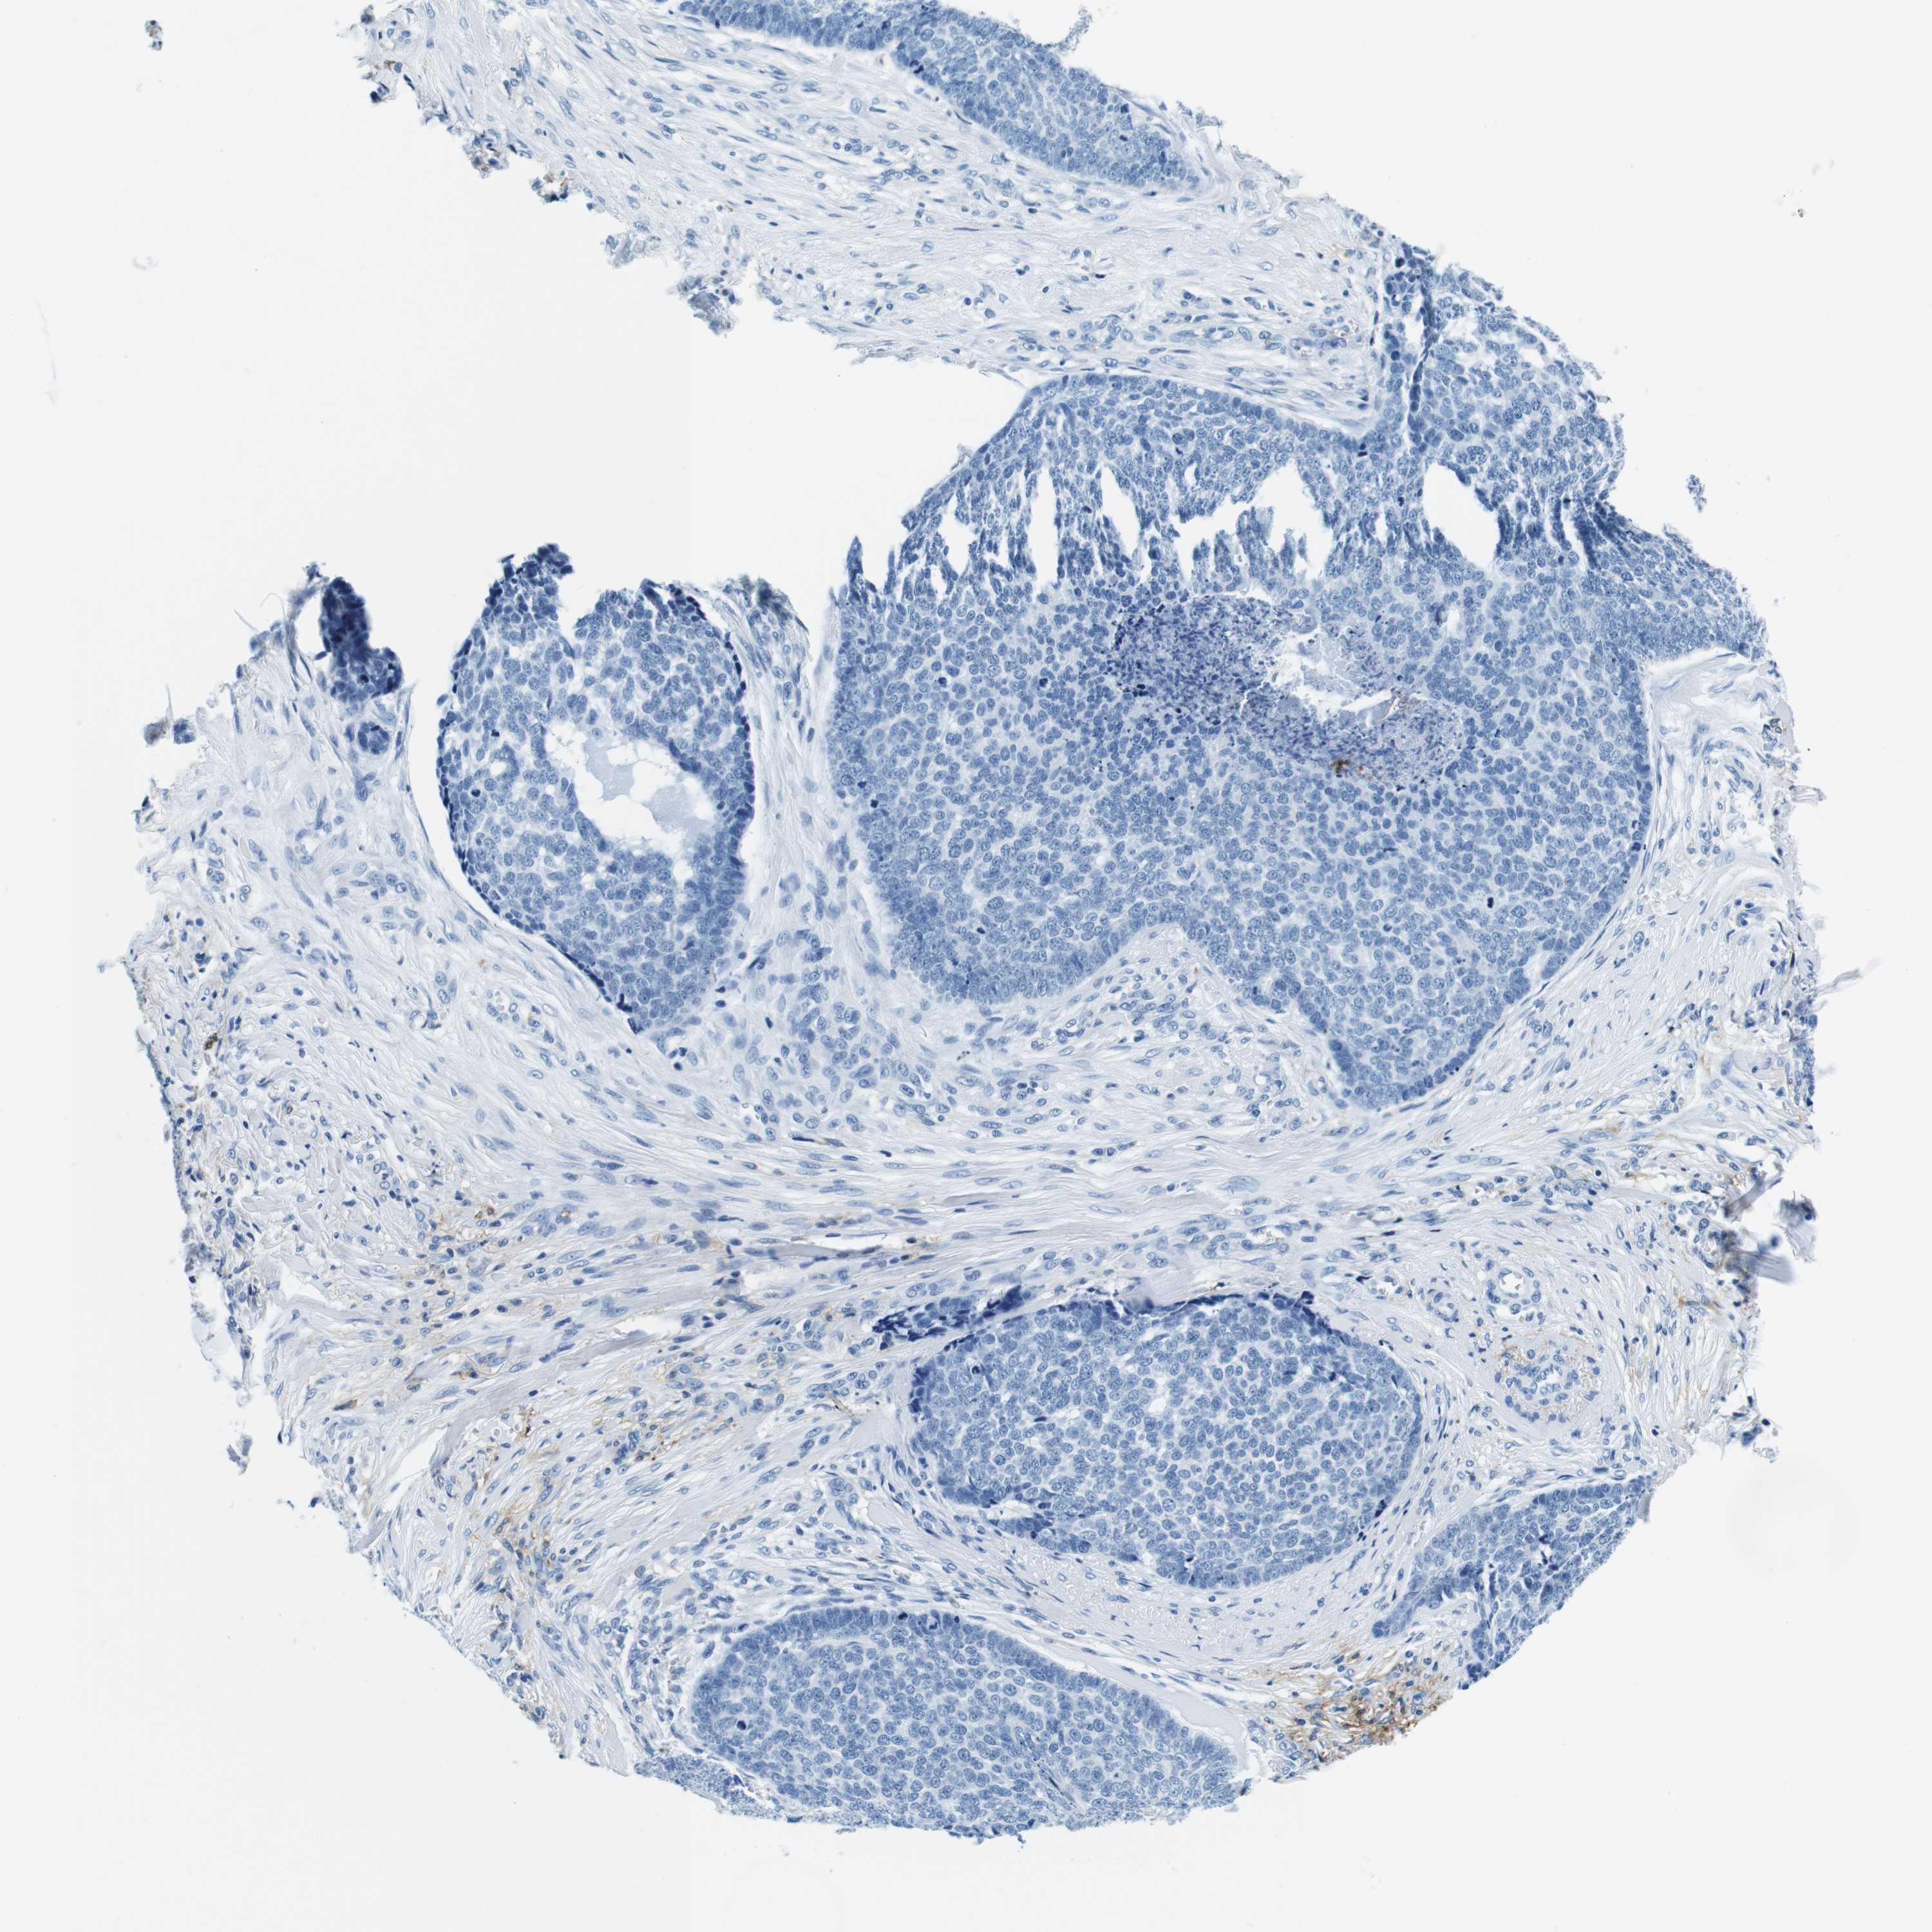

SKIN CANCER - Protein expressioni

A mouse-over function shows sample information and annotation data. Click on an image to view it in a full screen mode. Samples can be filtered based on level of antibody staining by selecting one or several of the following categories: high, medium, low and not detected. The assay and annotation is described here.

Antibody stainingi

Antibody staining in the annotated cell types in the current human tissue is reported as not detected, low, medium, or high, based on conventional immunohistochemistry profiling in selected tissues. This score is based on the combination of the staining intensity and fraction of stained cells.

Each image is clickable and will lead to virtual microscopy that enables deeper exploration of all samples and also displays staining intensity scores, fraction scores and subcellular localization as well as patient and tissue information for each sample.

Antibody CAB034021

Basal cell carcinoma

Squamous cell carcinoma, NOS

Squamous cell carcinoma, metastatic, NOS

Squamous cell carcinoma in situ, NOS

Adnexal tumor, benign